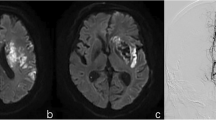

Infarct volume showed average performance with an AUC of 0.678 in distinguishing good and poor clinical functional outcomes in ischemic stroke (Fig. 2). Eleven radiomics parameters (supplementary material lists the implication of the 11 radiomics features) showing nonzero coefficients were finally obtained in the training cohort (Fig. 3a–c). Figure 3d shows the comparisons of radiomics scores between these two groups in both training and validation sets. Patients with poor outcome generally had higher radiomics scores than those with good outcomes. The Wilcoxon test showed that radiomics scores differed significantly between the good and poor outcome groups [−0.65 (−1.25, −0.03) vs. 0.10 (−0.42, 0.52); p < 0.005] in the validation set. The novel radiomics signature also performed well in distinguishing good and poor clinical functional outcomes with an AUC of 0.69 (0.59–0.78) in the validation set.

Radiomics transforms medical images into quantitative indexes through high-throughput extraction by data-assessment algorithms for predicting important clinical outcomes [13, 28]. However, there are few published reports applying radiomics to explore the functional outcomes of ischemic stroke cases, leaving a gap in knowledge. A previous study reported that DWI could identify lesions with a probability of 90% within the first 3 h of symptom onset [29]. Therefore, VOIs were delineated on DWI images in this study. The current work revealed that DWI–based radiomics had AUCs of 0.70 and 0.69 in the training and validation cohorts, respectively.